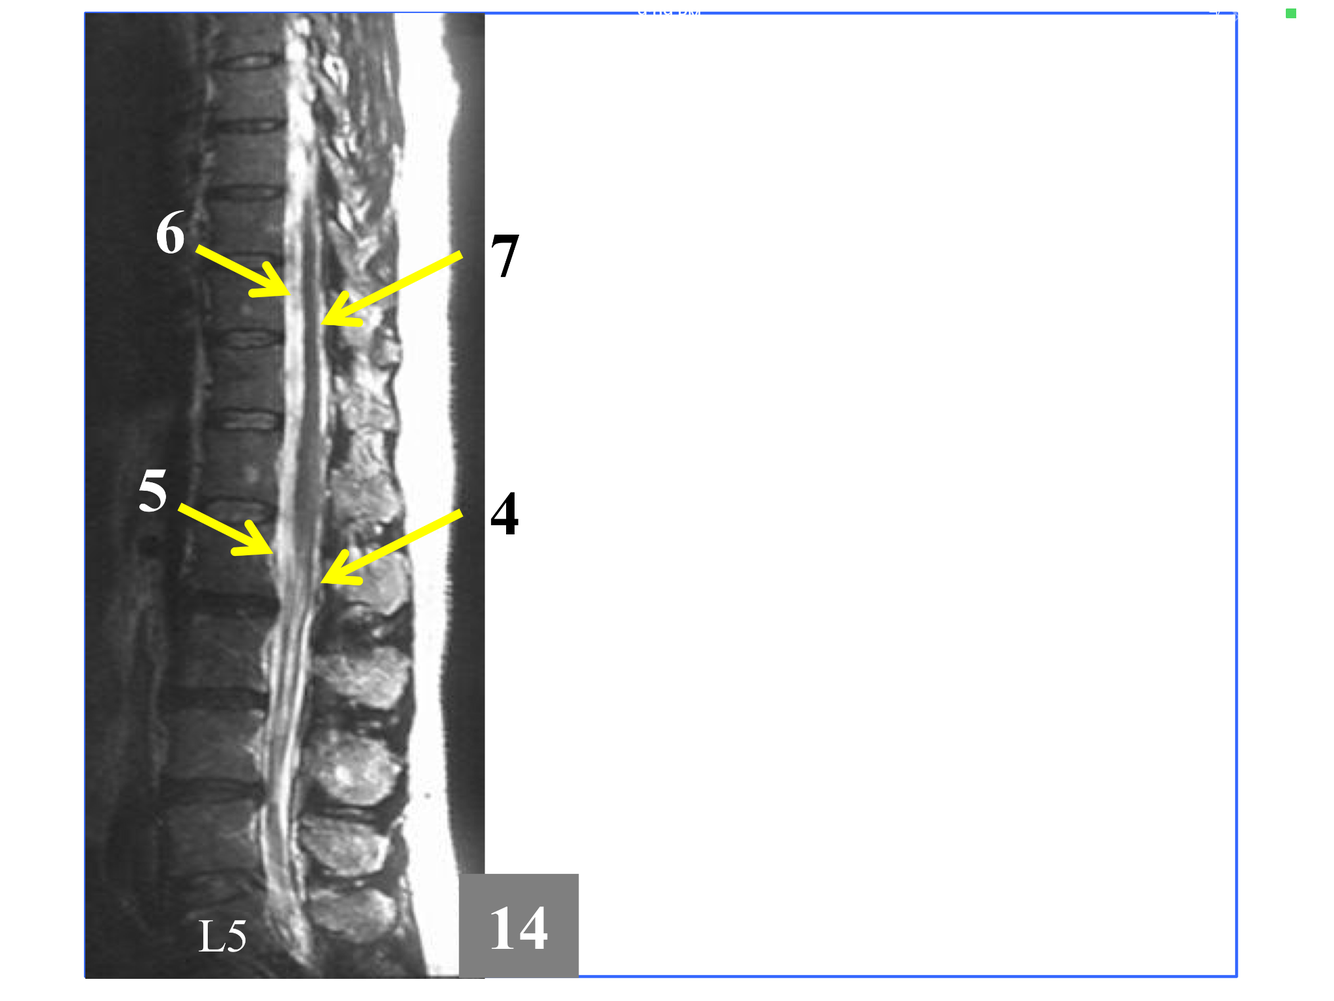

*Immediately above the conus, which is at L1-L2